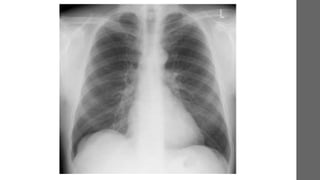

Radiografia de tórax

Espirometria

Bronquiectasias, pneumonia

persistente, sarcoidose e

tuberculose

Radiografia de tóraxMAISCOMUM

• Investigação Radiografia de tórax e espirometria